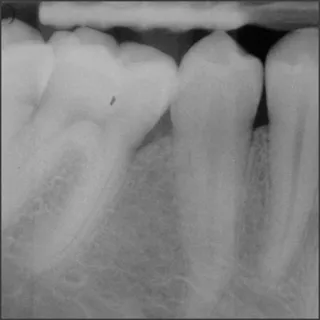

Before treatment with Straumann® Emdogain®.

Courtesy of Prof. Giovanni Zucchelli